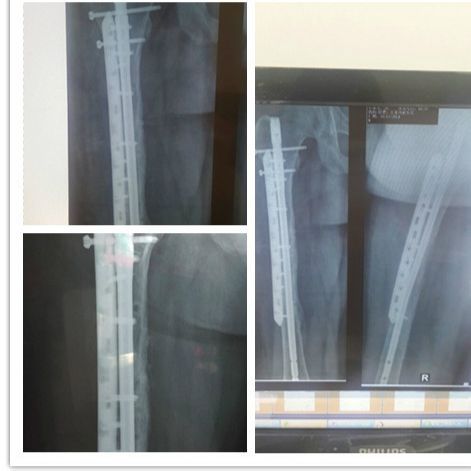

去年11月份车祸到现在,过去了7个月,期间的酸甜苦辣,这里的每个人都能理解,这苦谁受谁知道,到现在,已经上班一个月了,髓内钉下楼的时候会顶着膝盖疼,其他基本正常

回复@djkvfduknvcdyj :是胫腓骨开放粉碎性骨折,远端,大概5个月的时候脱拐,双拐时间比较长,都不要着急脱拐,反正不影响锻炼

回复@哭不出来518 :是膝盖下一点,感觉是髓内钉上面的横钉部位,也不知道学名怎么称呼。

住院20天,由于为远端,开放伤口,恢复的比较慢,加上一个年轻医生经验不足,差点伤口感染,因为用vsd,医生把那塑料膜包裹住了腓骨刀口,大家都觉得这样有问题,说塑料包伤口不行吧,年轻医生说,这种膜是透气膜,不是我们认为的普通塑料膜,半信半疑的用了,第二天就发现伤口红肿,有少许脓液,

告诉医生后,医生消毒后,用纱布蘸满了消毒液又敷在伤口上,第三天明显红肿,刀口脓液更多,医生说要是不行的话再用一块vsd,伤口肿的似乎要把缝线涨开。